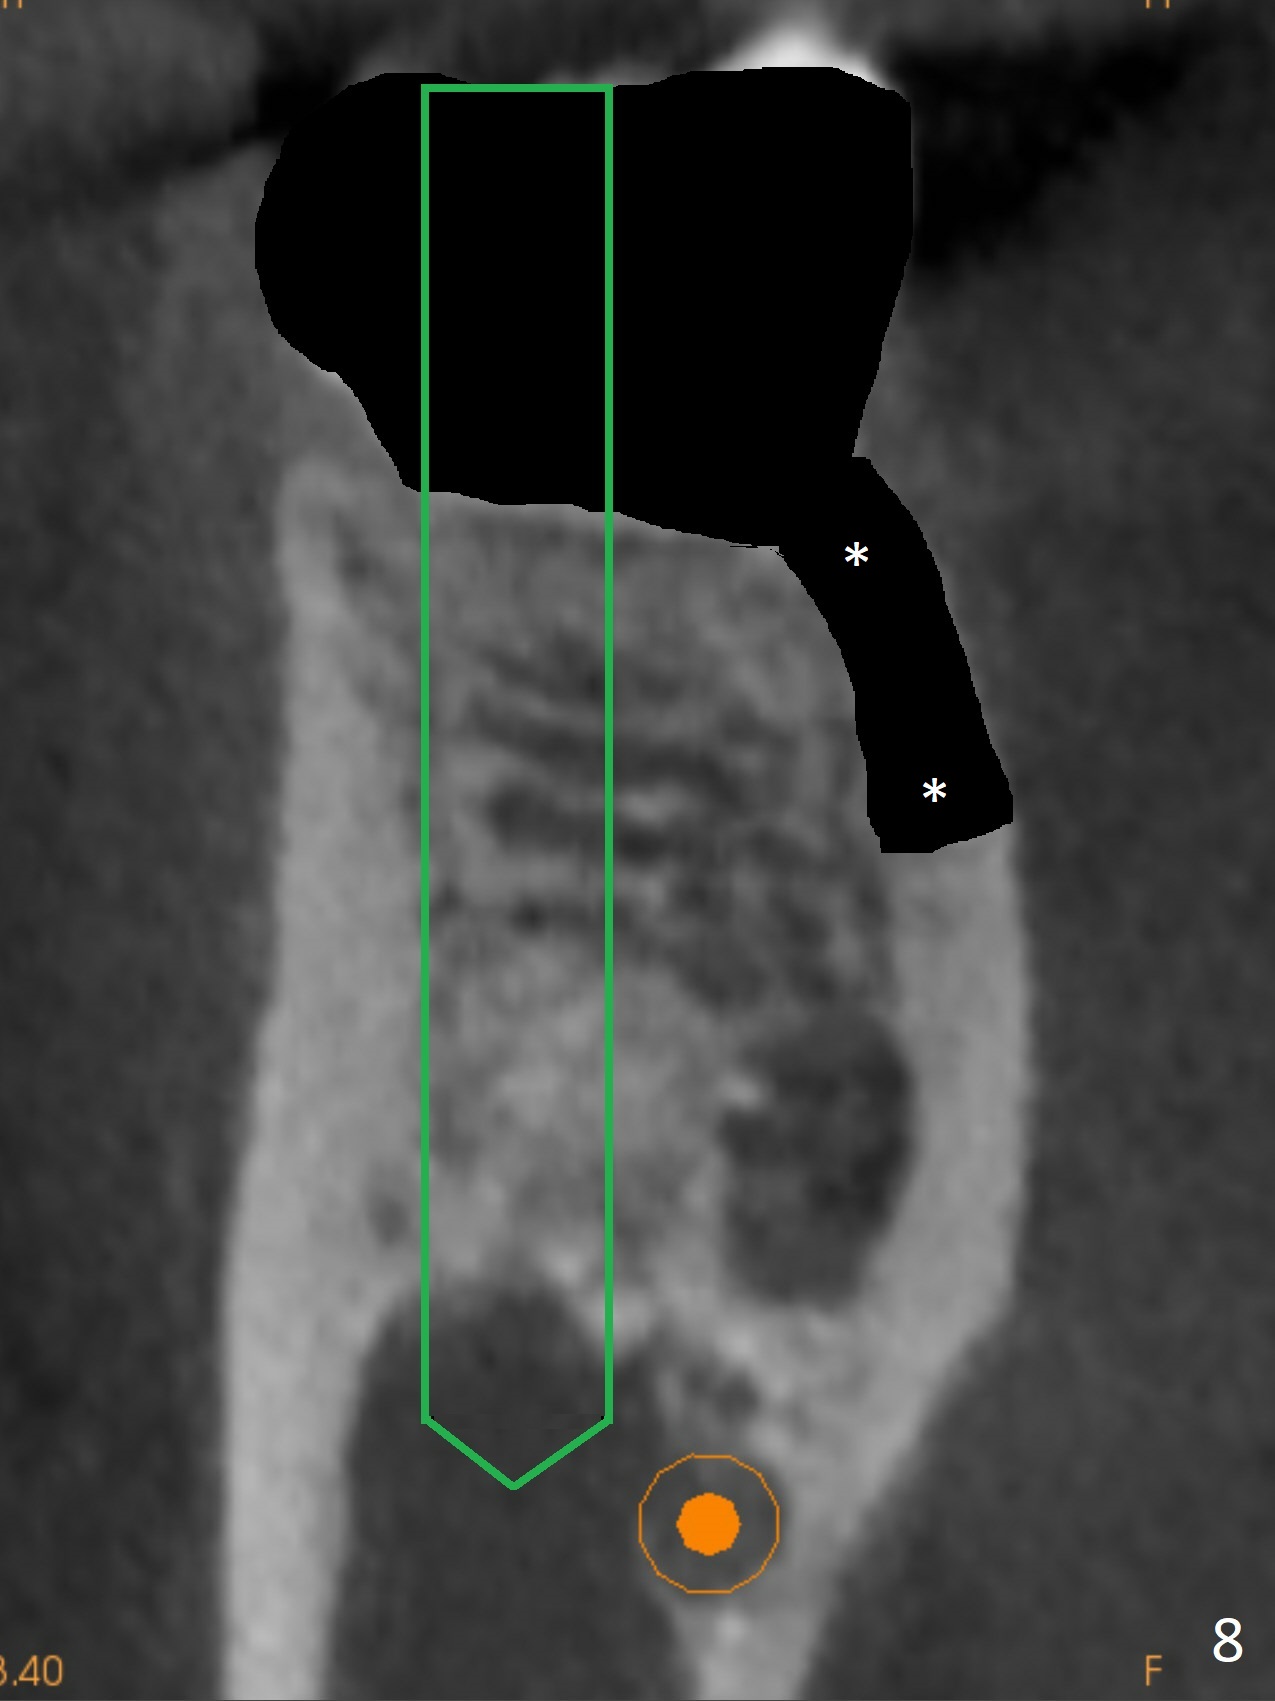

Fortunately no paresthesia is reported postop. Why is the Inferior Alveolar Canal not violated? Fig.7 is a coronal section of CBCT taken for a 40-year-old man at the lower 1st molar (at the septum). At the region, the Canal (brown circle) is close to the lingual plate (L). Because of severe bone loss of the lingual plate of this case (Fig.8 *), osteotomy is intentionally created buccal (green). The deep osteotomy may not contact the Canal, while the hemorrhage may stem from the medullary space (M in Fig.4,7). Bone morphology at the coronal end of the implant apparently changes 4 months postop, suggesting osteointegration (Fig.9). Impression is taken. Bone density around the implant at the crest seems to increase (Fig.10), while there is no soft tissue deficiency 10 months post cementation (Fig.11). The bone appears to regenerate toward the abutment, particularly distally, 14.5 months post cementation (Fig.12). Periimplantitis develops (bleeding on water pik and erythematous and tender buccal gingiva) 1 year 7 months post cementation (Fig.13,14). The 1st three threads are exposed (*). Bone graft with PRF and 6-month membrane or Cytoplast will be needed. Pain disappears 3 days of oral antibiotic. The gingiva looks healthy 1 month later when he returns for bone graft (Fig.15). But the lingual gingival cuff is not so healthy when the crown/abutment is removed (Fig.16 <). Bone graft is not done. For those patients with suboptimal oral hygiene, implants should be placed as low as possible, better with guide for precision.